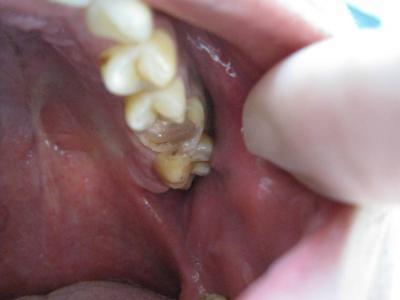

先生が歯を削っている最中、面白がって

写真撮ってやろうかぁなんていうもんだから

遠慮なく撮ってもらいました。

リアルなんでスルーされても結構ですよ。

この後、全て歯がなくなりました。根元少し残して・・・。